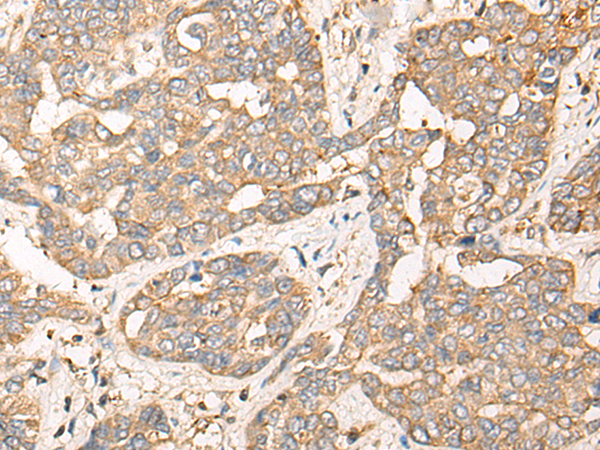

IHC positive control: |

Human liver cancer and Human esophagus cancer |

IHC Recommend dilution: |

30-150 |